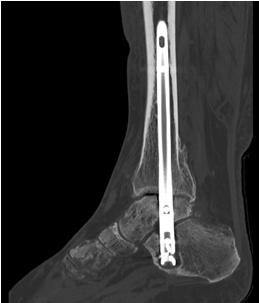

Implantation des Nagels und BV-Kontrolle (Video 5). Schließlich erfolgt die Verriegelung des Nagels über entsprechende Zielvorrichtungen. Bei einigen Nageltypen gibt es nageleigene Kompressionsmechanismen, die eine zusätzliche Drucksteigerung im Bereich der Arthrodeseflächen des ehemaligen oberen und unteren Sprunggelenkes erlauben (Video 6). Die abschließende BV-Kontrolle in beiden Ebenen sollte eine regelrechte Stellung der Arthrodese mit 90° - Stellung im Rückfuß, in der anderen Ebene mit einem Rückfußvalgus von ungefähr 5° zeigen.

• Primäre oder posttraumatische Arthrose des OSG und USG (Abbildung 1, Abbildung 2).

• Revision einer gescheiterten Fusion des OSG/ USG (Abbildung 3, Abbildung 4).